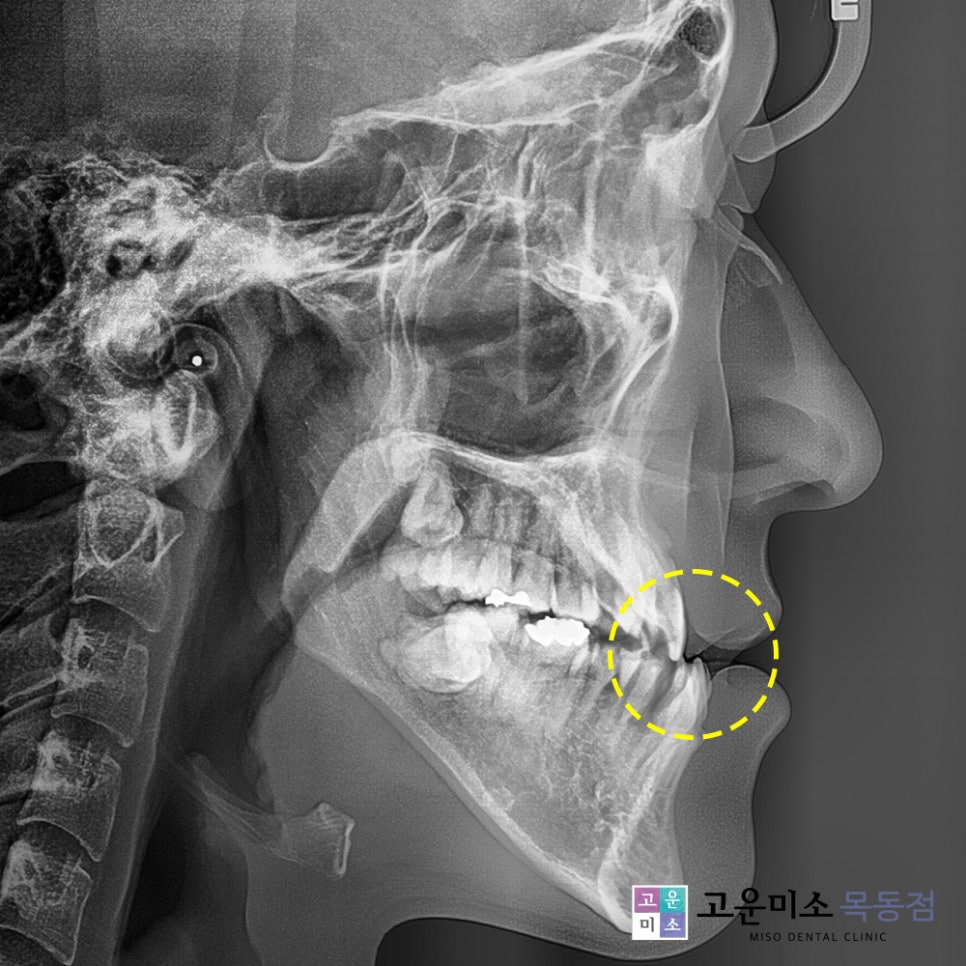

목동치아교정, 목동 연세고운미소치과에서는

골격의 상태를 정확히 확인하기 위해

엑스레이 분석을 진행하였습니다.